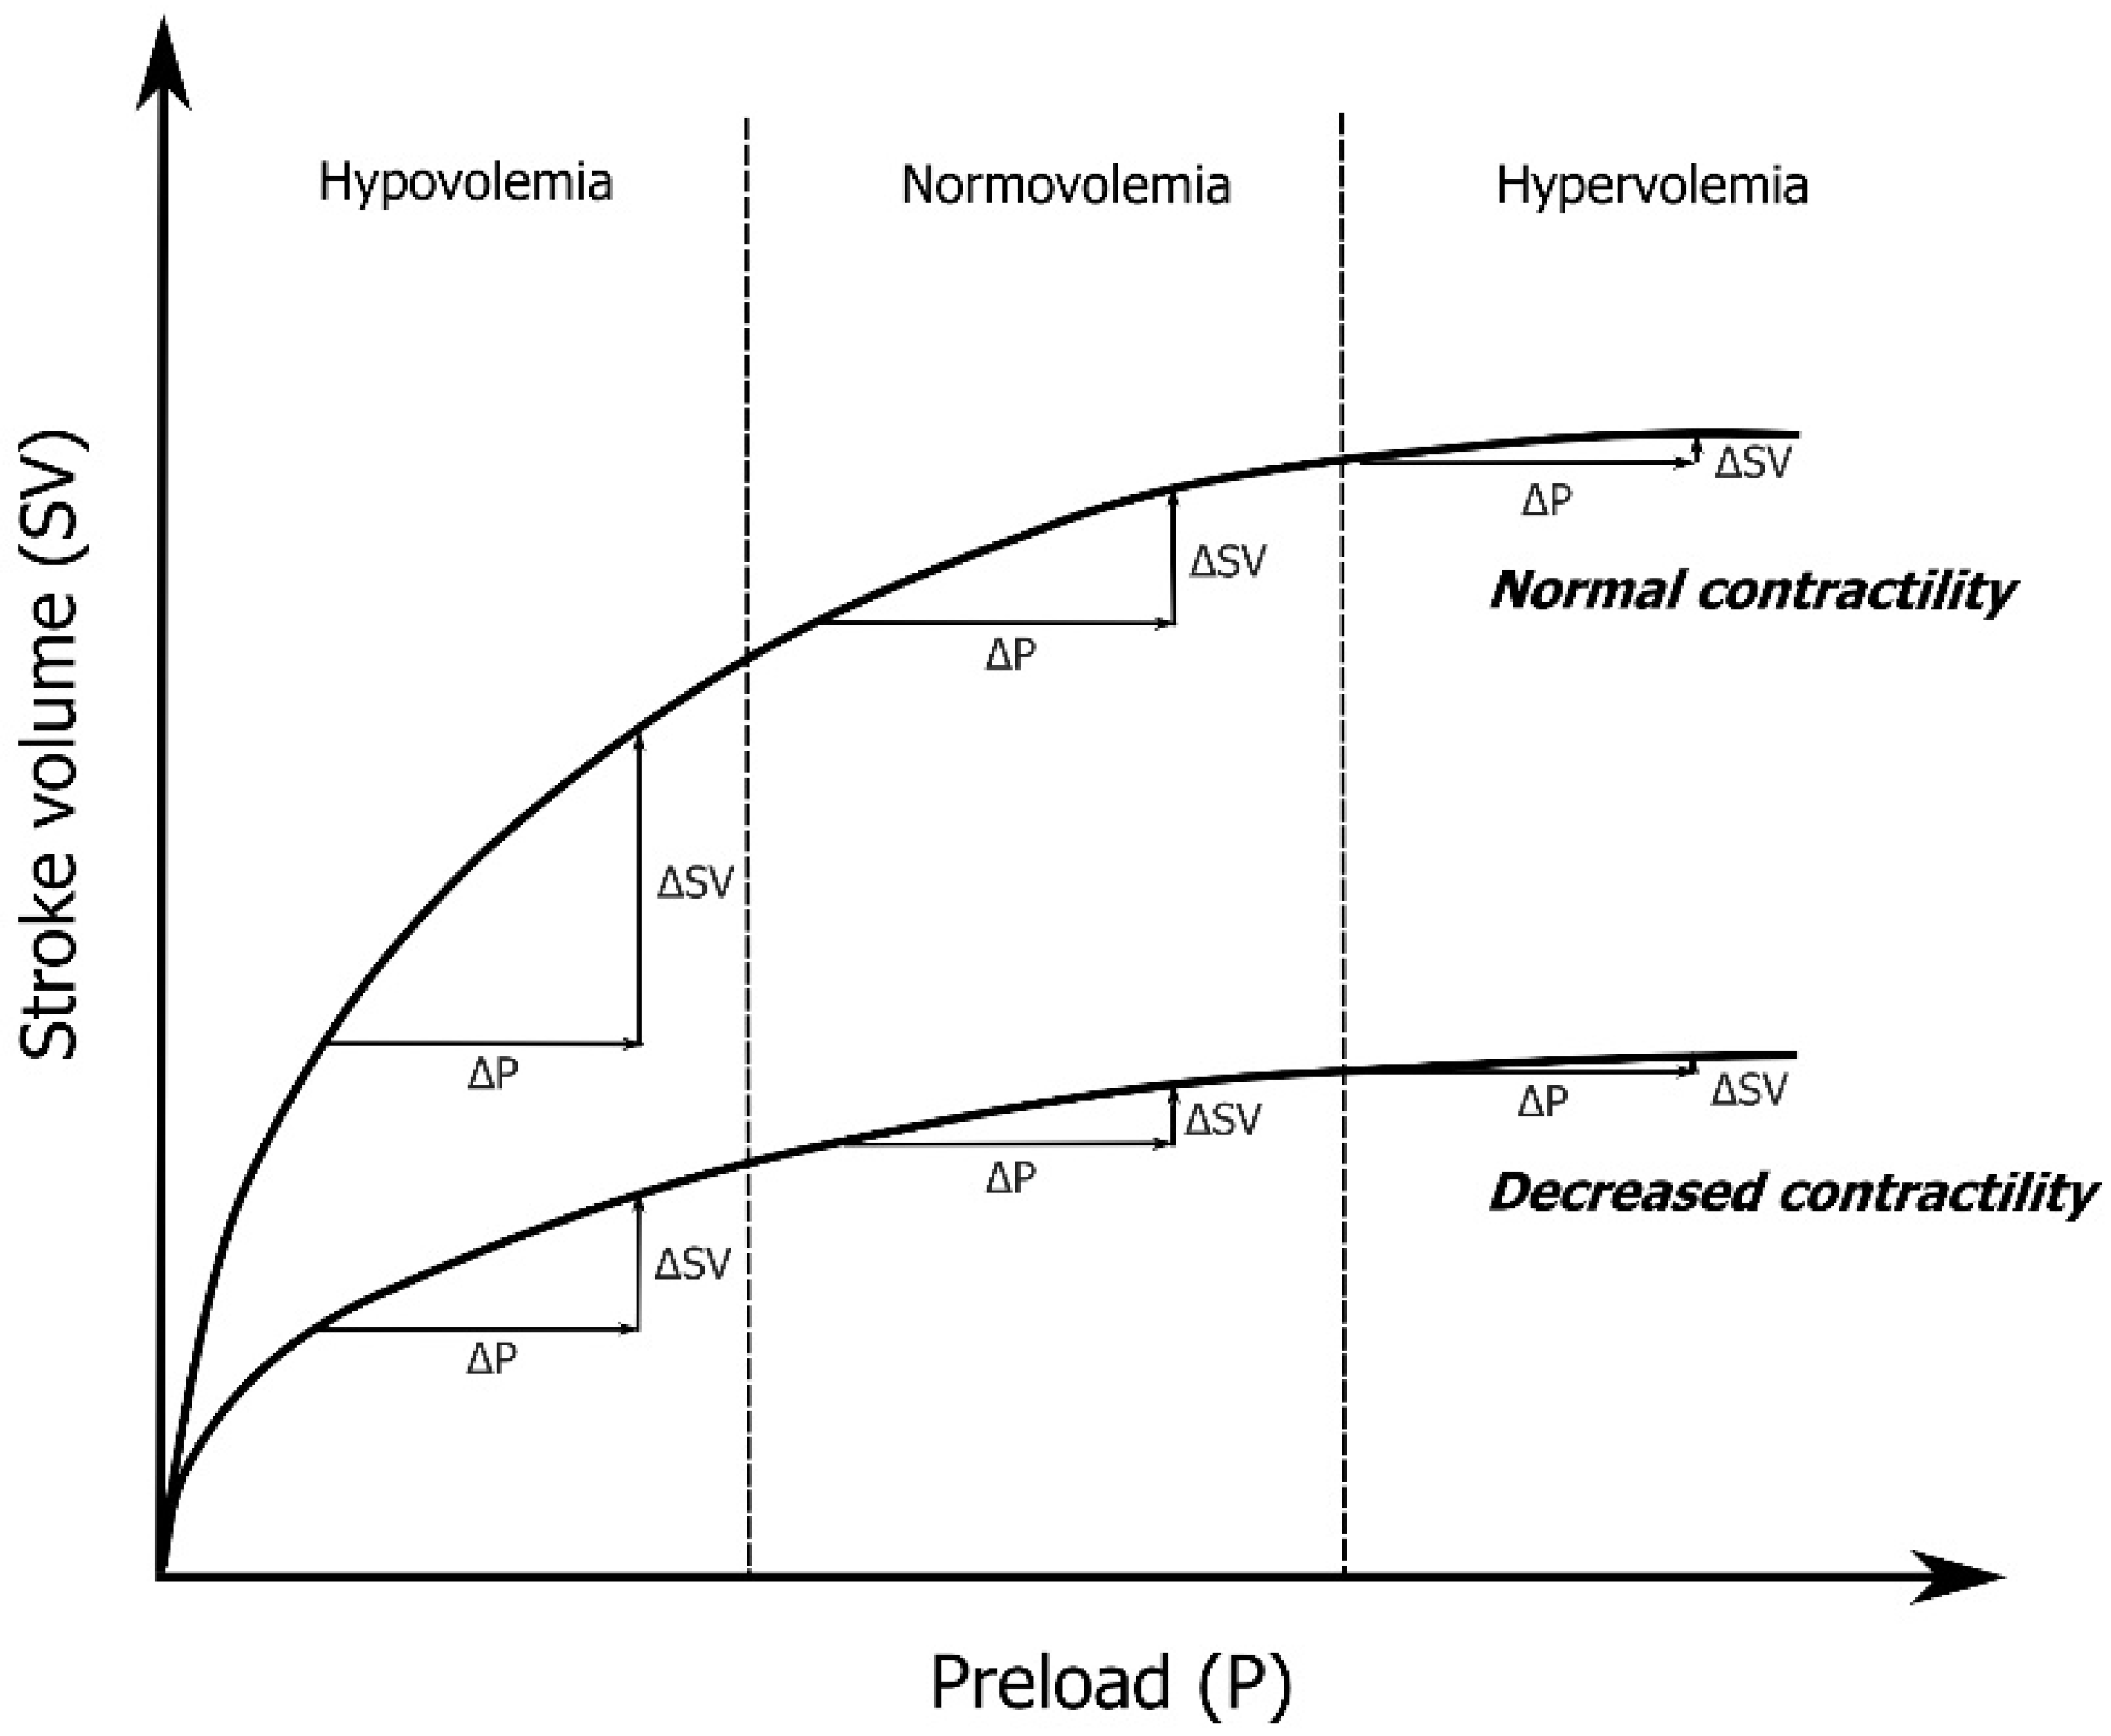

:1. Introduction